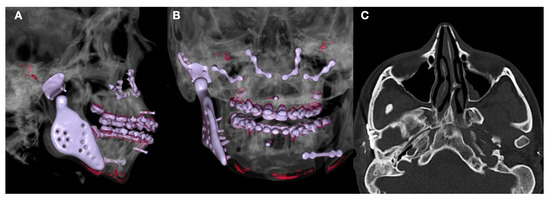

1.3. Clinical Conditions Related to Use of TMJ Replacement

- Volume and Size Augmentation of the Mandibular Condyle

- Volume and Size Reduction of the Mandibular Condyle

- Malformations, Pathology, or Trauma of the Mandibular Condyle